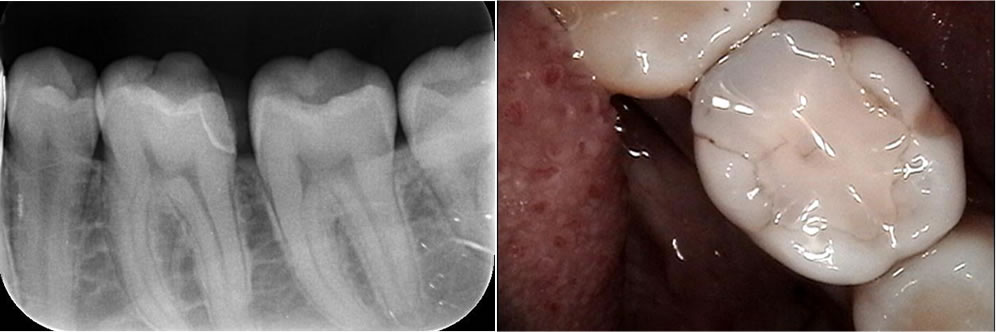

むし歯治療後にセラミックオンレーで修復した症例

むし歯治療後にセラミックオンレーで修復した症例 撮影したレントゲンにて左上5番目の後ろにむし歯が発現していたため、治療することとなりました。 むし歯の除去 麻酔の針による痛みが出ないよう表面に麻酔を塗り、感覚が鈍くなった […]